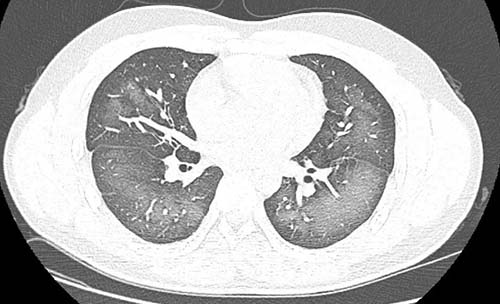

正常情况下,肺内充满了大量气体,因此密度很低,进行放射检查时,X射线穿过肺部时的衰减少,会显示出呈黑色图像。

相反,如果肺部有大量病变或炎性渗出增多,或存在广泛的占位病变,肺部的密度越大,X射线通过时衰减就会增多,图像中就显示白色。

如果病变严重,图像中肺的大部分(达到70%~80%)变白,称之为“白肺”。

出现“白肺”时,由于肺部有效面积减少,炎性渗出增多,换气功能障碍,患者常有呼吸困难、胸闷、气喘、咳嗽、严重缺氧等表现,严重时可发生呼吸衰竭、多器官功能障碍,甚至有生命危险。